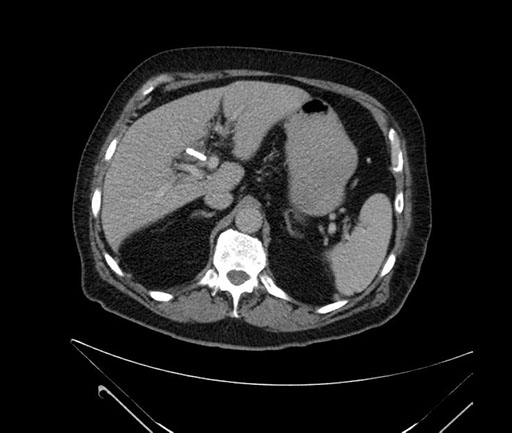

Axial - stented